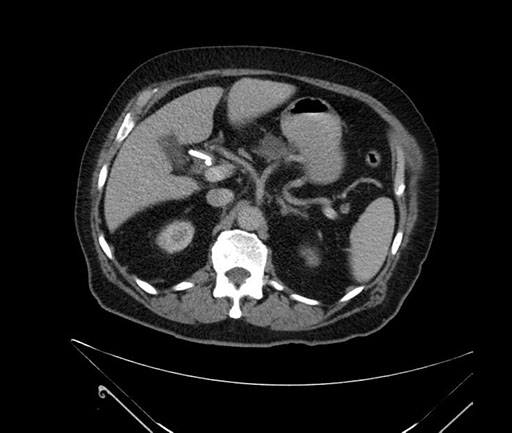

Whipple (pancreaticoduodenectomy) [case 7]

Imaging Analysis

Look through the patient's CT scan to identify any areas of concern for the necessary procedure.

Axial - stented